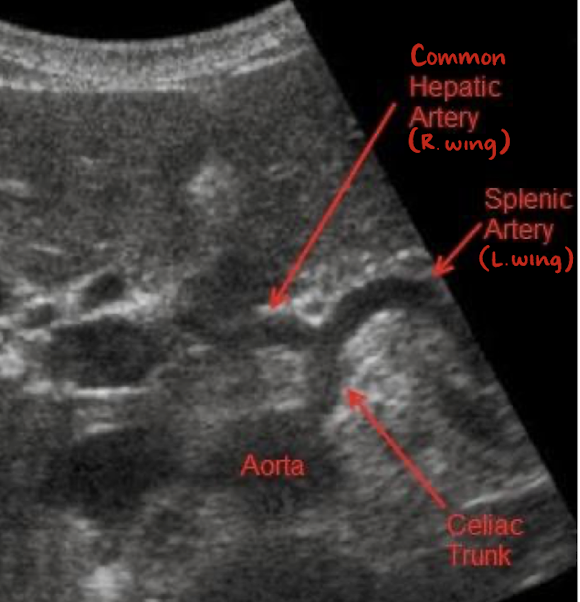

celiac trunk/artery/axis

1st branch off AO

measures less than 1 cm

“seagull sign”

consists celiac trunk, common hepatic artery (right wing), and splenic artery (left wing)

branches of CA

common hepatic artery

splenic artery

left gastric artery